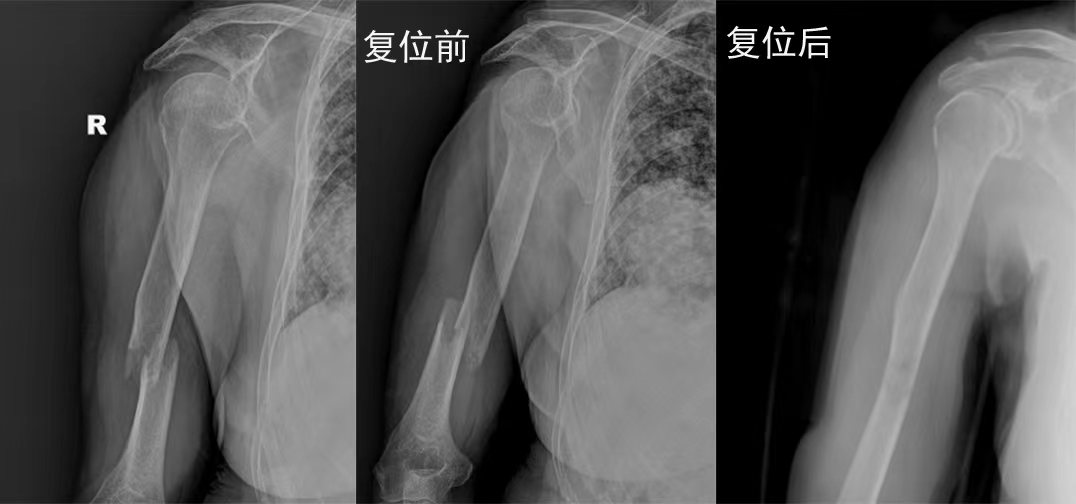

梁氏正骨-梁光兴正骨案例